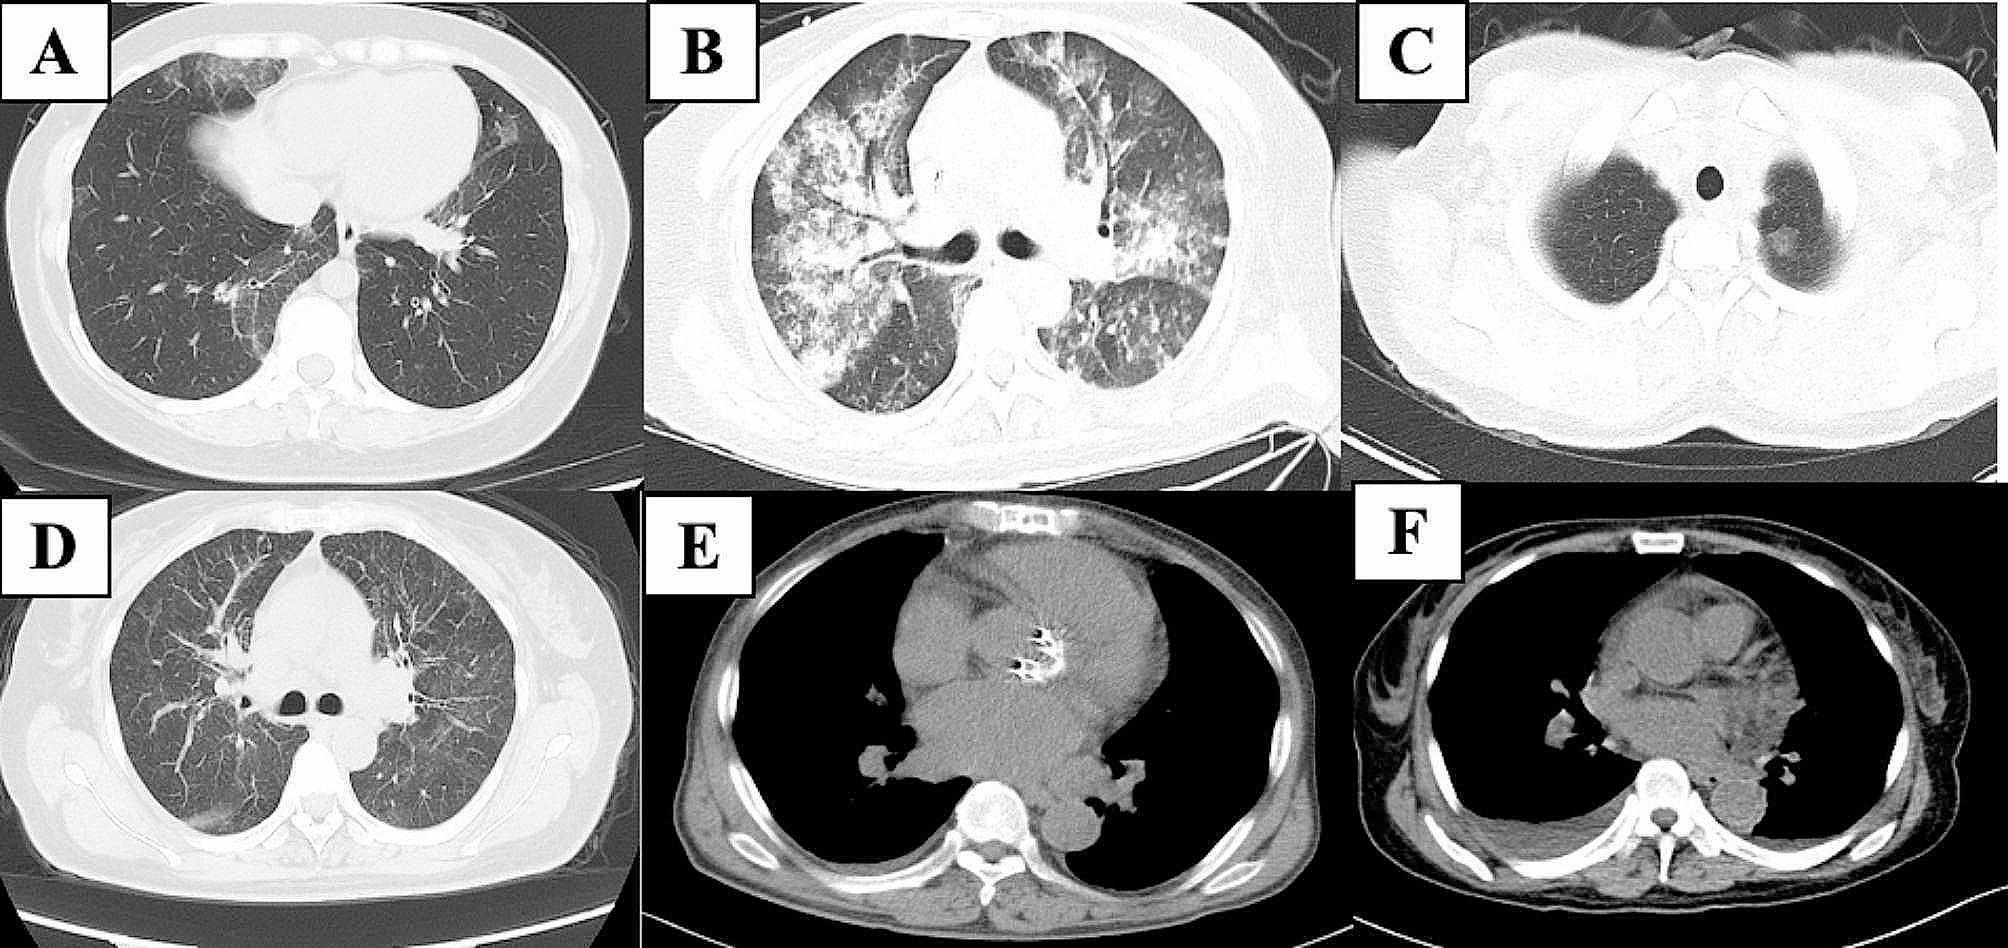

Results: The 10 patients with pulmonary involvement (2 males; median age, 53 years) included three patients with type I cryoglobulinemia and seven patients with mixed cryoglobulinemia. All of 10 patients were IgM isotype cryoglobulinemia. All type I patients were secondary to B-cell non-Hodgkin lymphoma. Four mixed patients were essential, and the remaining patients were secondary to infections (n = 2) and systemic lupus erythematosus (n = 1), respectively. Six patients had additional affected organs, including skin (60%), kidney (50%), peripheral nerves (30%), joints (20%), and heart (20%). The pulmonary symptoms included dyspnea (50%), dry cough (30%), chest tightness (30%), and hemoptysis (10%). Chest computed tomography (CT) showed diffuse ground-glass opacity (80%), nodules (40%), pleural effusions (30%), and reticulation (20%). Two patients experienced life-threatening diffuse alveolar hemorrhage. Five patients received corticosteroid-based regimens, and four received rituximab-based regimens. All patients on rituximab-based regimens achieved clinical remission. The estimated two-year overall survival (OS) was 40%. Patients with pulmonary involvement had significantly worse OS and progression-free survival than non-pulmonary involvement patients of cryoglobulinemia (P < 0.0001).

Conclusions: A diagnosis of pulmonary involvement should be highly suspected for patients with cryoglobulinemia and chest CT-indicated infiltrates without other explanations. Patients with pulmonary involvement had a poor prognosis. Rituximab-based treatment may improve the outcome.